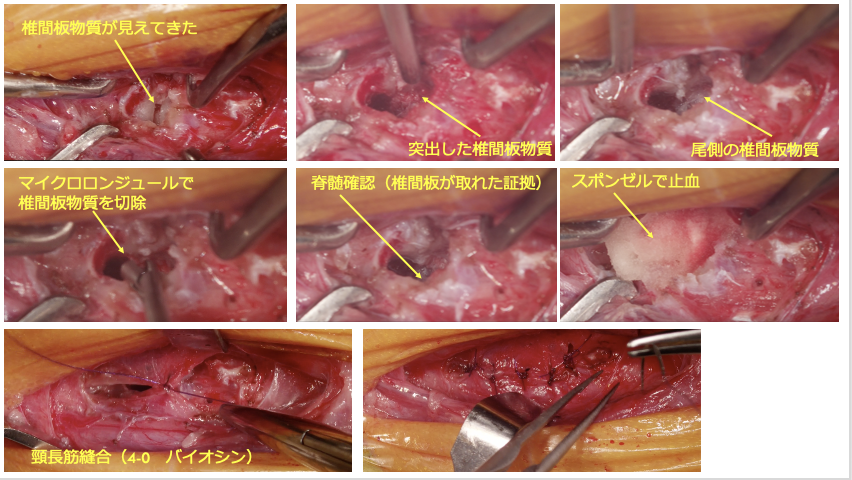

左前肢破行、後肢ふらつきを主訴に来院しました。CT・MRI撮影より、C5-6の椎間板ヘルニア、小脳背側のくも膜下嚢胞が認められました。症状が軽度から中等度、また小脳背側にくも膜下嚢胞が認められ麻酔のリスクなどを考慮し、まずは内科療法から行いました。2か月後症状の改善が認められず、症状も進行し、起立・歩行困難となりました。

犬の頸部椎間板ヘルニアとは、頚椎と頚椎の間の椎間板が飛び出して、脊髄や神経を圧迫してしまう病気です。症状は、軽度な場合は首を動かすのを嫌がる、抱き上げるとキャンと鳴く、元気食欲低下などが認められます。中等度から重度になると、頸部の痛みが強くなり、ふらつき、四肢麻痺となり起立・歩行不能となります。診断には、CT・MRIが必要となります。軽度から中等度の場合は、内科的に治療することもありますが、重度の場合は、外科的介入が必要となります。外科的な方法としては、腹側スロット術(ベントラルスロット術)が一般的に行われます。椎間板ヘルニアが多発する場合は、背側椎弓切除術を行います。

左前肢破行、後肢ふらつきを主訴に来院しました。CT・MRI撮影より、C5-6の椎間板ヘルニア、小脳背側のくも膜下嚢胞が認められました。症状が軽度から中等度、また小脳背側にくも膜下嚢胞が認められ麻酔のリスクなどを考慮し、まずは内科療法から行いました。2か月後症状の改善が認められず、症状も進行し、起立・歩行困難となりました。

C5-6椎間板ヘルニア、小脳背側くも膜下嚢胞

C5-6椎間板ヘルニア、くも膜下嚢胞と診断した